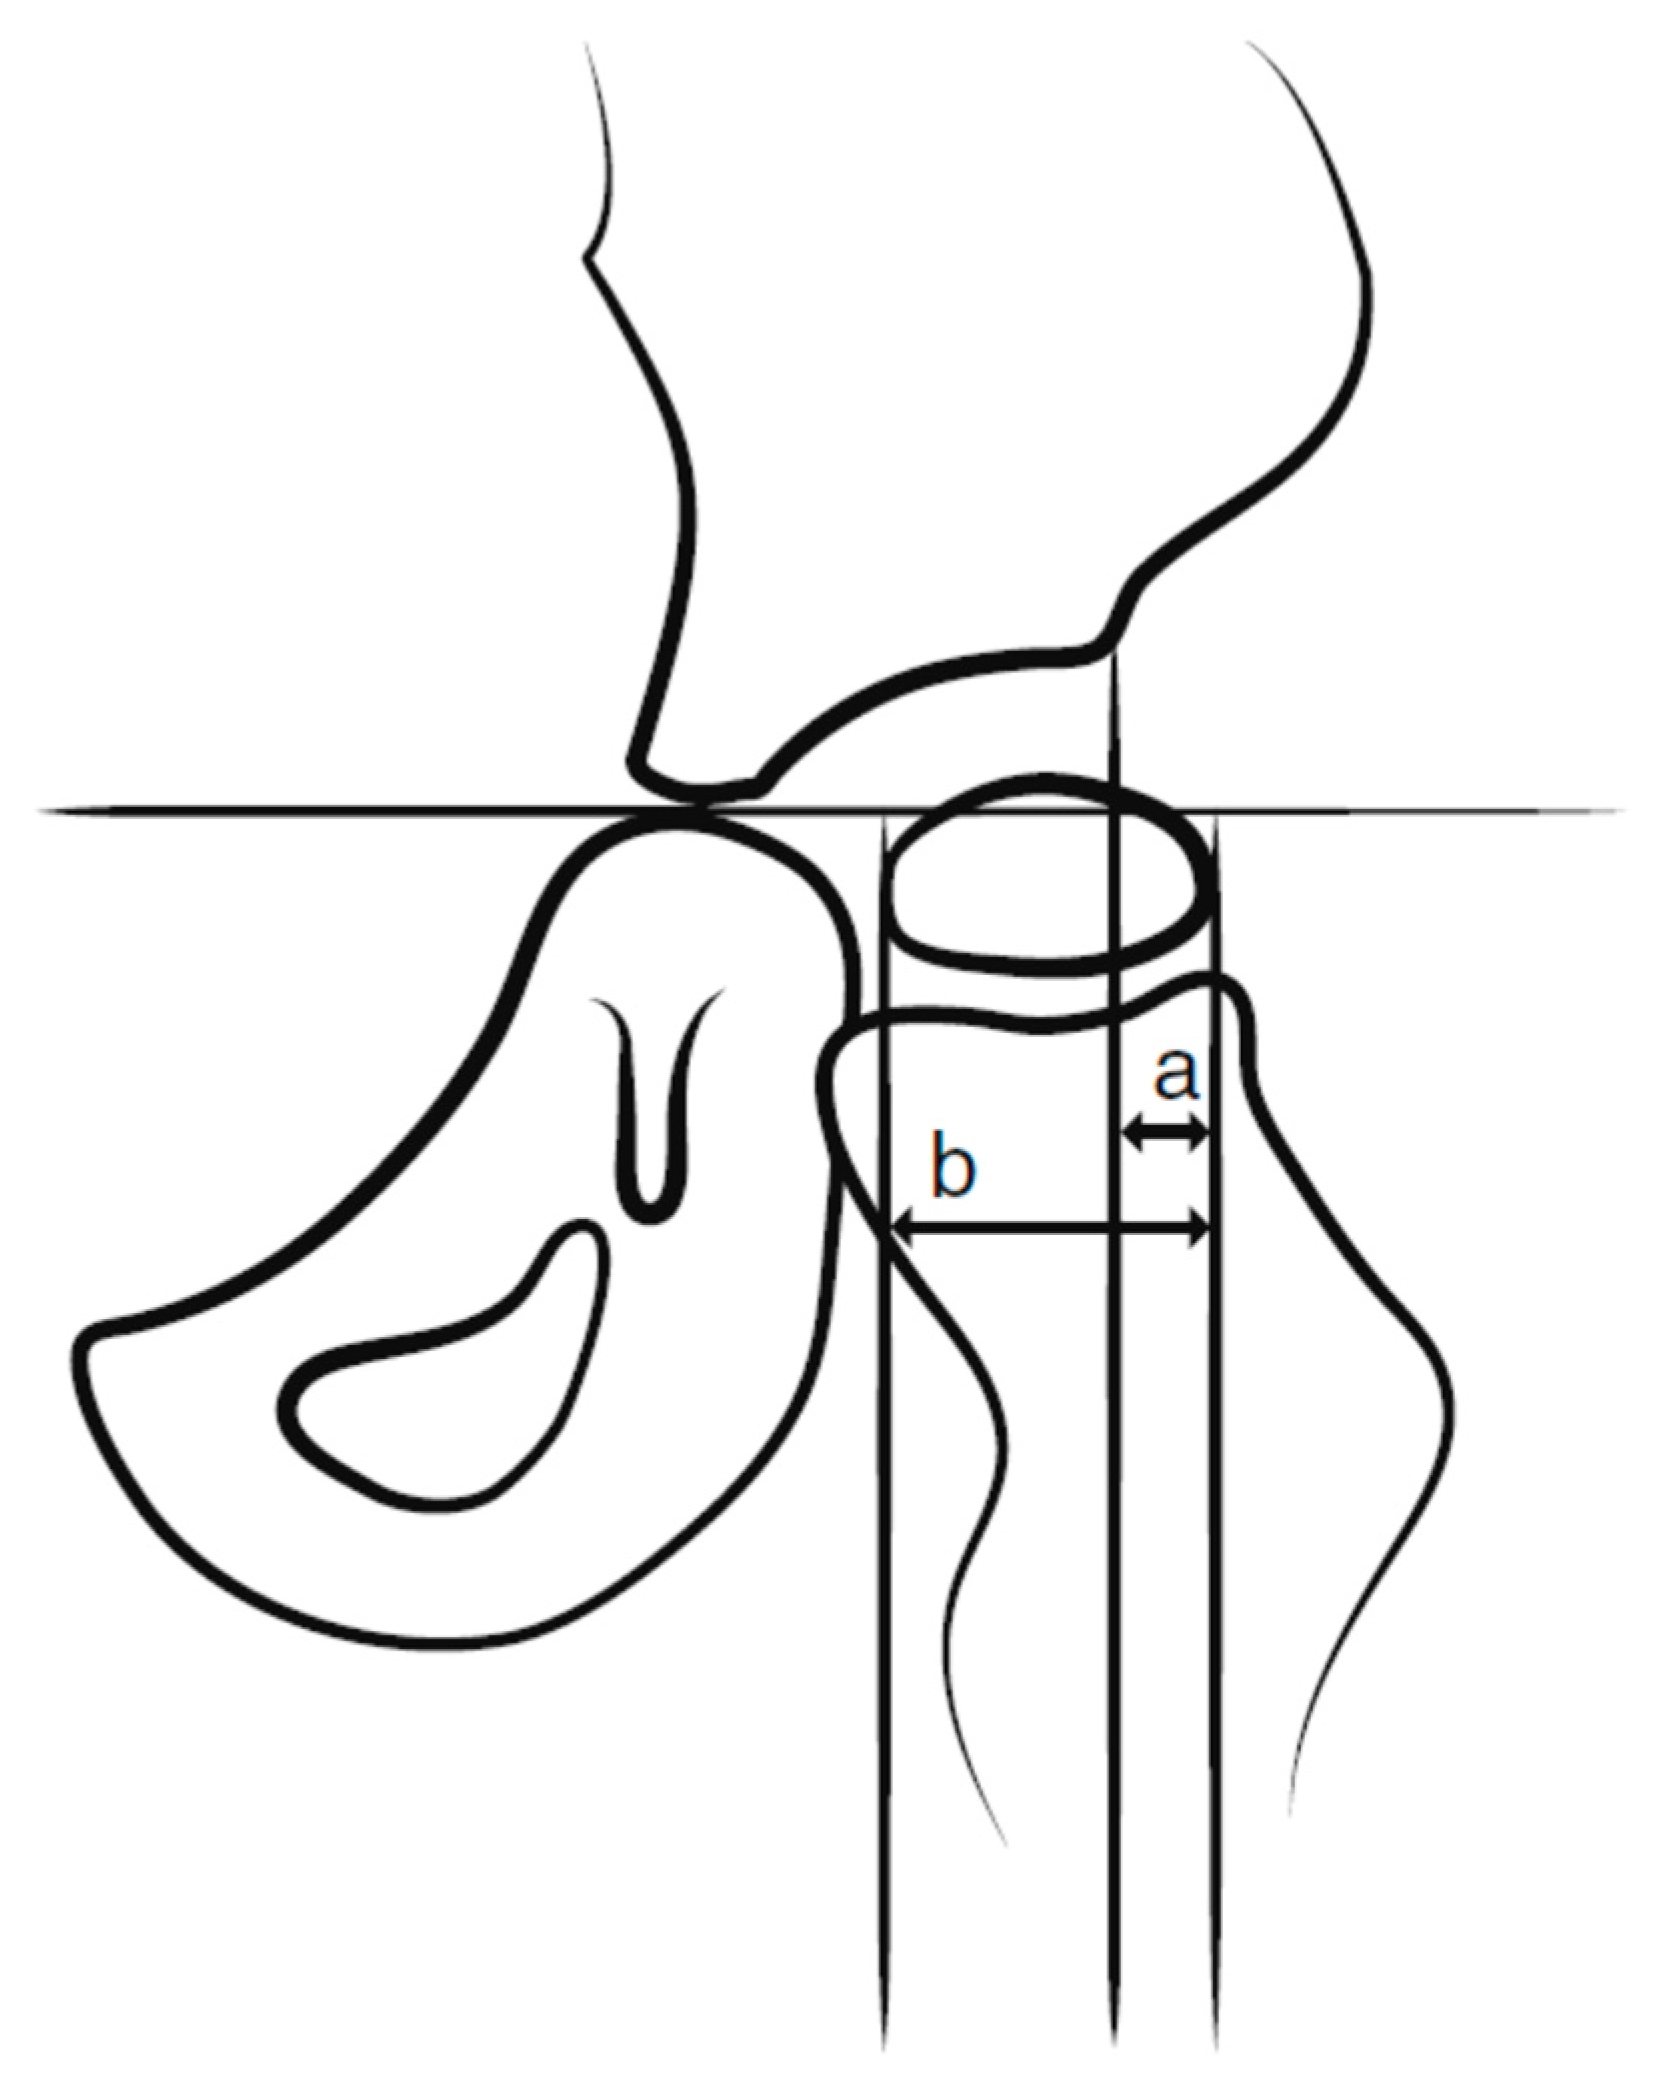

This was a retrospective registry study based on data from the CPUP and Statistics Sweden. In the CPUP, the gross motor function is classified by the internationally used Gross Motor Function Classification System (GMFCS); this system is a five-level scale in which level I represents the highest level and level V represents the lowest level of gross motor function [18,19]. All children up to 8 years of age within the GMFCS levels III–V are radiographically examined with a pelvic anteroposterior view annually and those within the GMFCS level II at 2 and 6 years of age. Children in level I are not examined radiographically provided that the child has a normal pain-free range of hip motion. After 8 years of age, the examination intervals are determined individually based on the results of previous examinations and clinical reports. The degree of displacement of the femoral head is measured with the Reimer’s Migration Percentage (MP), where MP 100% defines hip dislocation (Figure 2).

Figure 2. Measurement of hip migration percentage (MP). MP = a/b × 100.